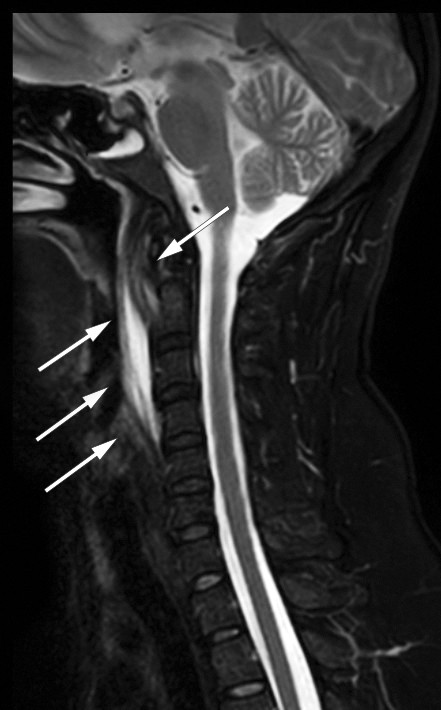

A cervical MRI confirmed the presence of fluid in the retropharyngeal space and oedema in the prevertebral soft tissue but ruled out spondylodiscitis (Figure 2). Calcific tendinitis was considered as a differential diagnosis, but when the patient's pain worsened, she was admitted to the otorhinolaryngology department for further examination. By now she had almost no mobility in her neck and could barely eat or drink due to the odynophagia. Examination revealed no bulging of the pharynx as would have been expected with an abscess, and she remained negative for leukocytosis. Treatment for tendinitis was started in the form of diclofenac 50 mg × 3 orally, with intravenous clindamycin 300 mg × 4 to cover infection. By the next day, the patient's symptoms had improved significantly, with increased mobility of the neck and reduced pain. Such a rapid response would be unlikely with a retropharyngeal abscess, and antibiotic treatment was therefore discontinued as infection was no longer suspected. By Day 3, after 24 hours without antibiotics, the patient's CRP level had halved, and she was discharged with a diagnosis of calcific tendinitis in the longus colli muscle and instructions to continue treatment with diclofenac 50 mg × 3 orally for one week. Blood cultures from samples taken on arrival were negative (results became available after discharge) and no further follow-up was required.

The amount of calcium can vary and does not correspond to the degree of inflammation (2). Secondary inflammatory changes may also be present, such as retropharyngeal effusion and oedema in prevertebral soft tissue, as seen on both CT and MRI in this patient (Figures 1 and 2). In patients with retropharyngeal abscess, contrast enhancement would be expected around the fluid collection, and possibly gas bubbles and local lymphadenopathy; these will be absent in cases of calcific tendinitis (2, 4). Our patient was nevertheless given antibiotics, as infection could not be completely ruled out.

Cervical MRI was also performed to rule out spondylodiscitis. MRI has high sensitivity for detecting inflammatory changes in and around the longus colli muscle, but is less sensitive than CT for detecting calcifications, and is therefore not the first choice (2).